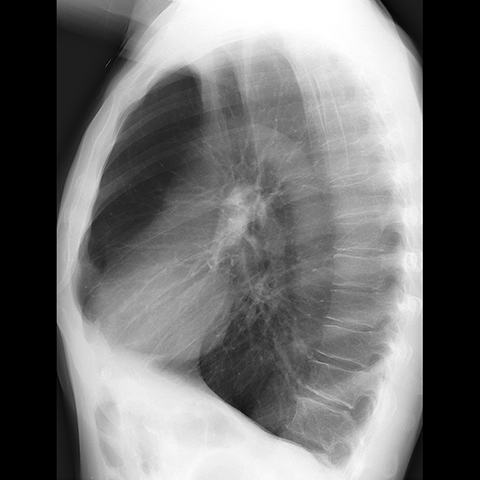

A 62 year-old male presents with chronic shortness of breath (Lateral Radiograph). [3 of 6]